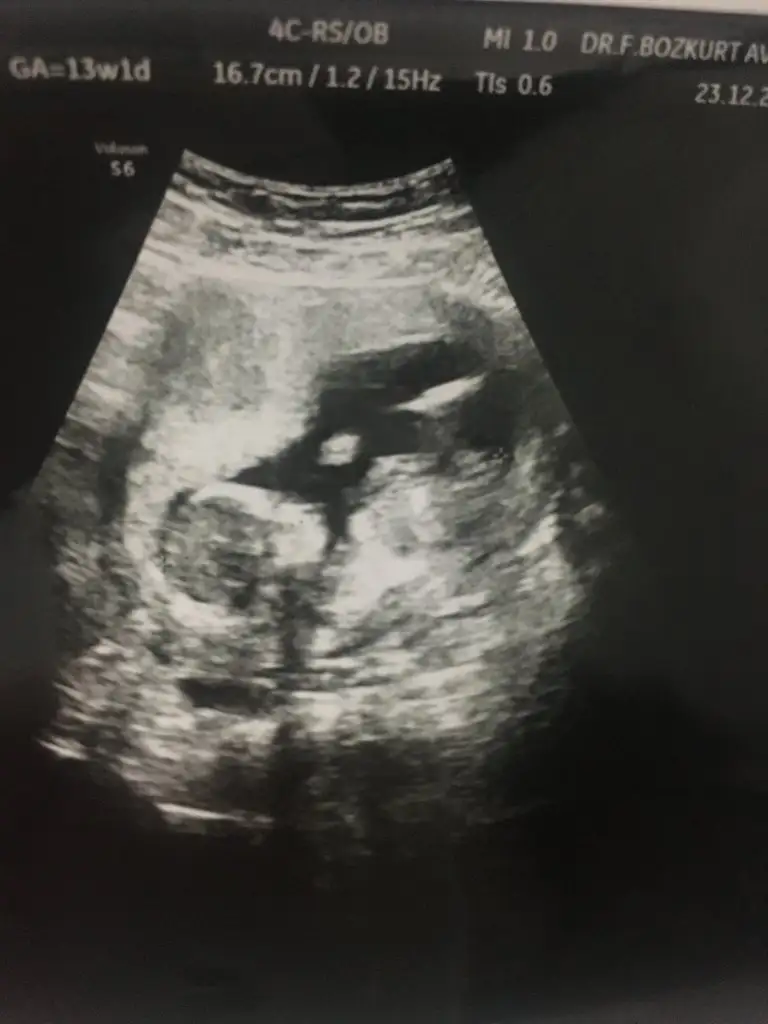

Merhabalar biraz büyüdük tekrar geldik 12+2 karından bakıldı bi tahmininiz varmı 😊